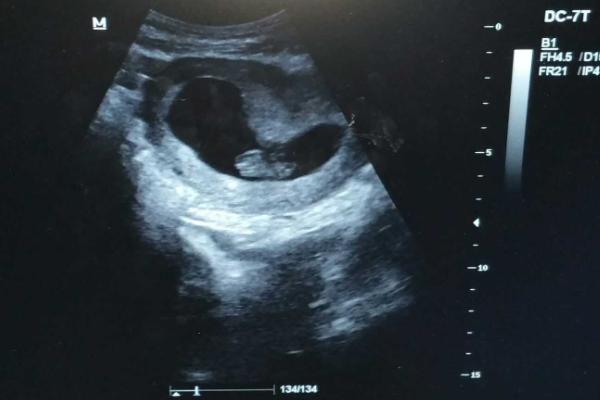

今年30岁,由于卵巢功能早衰的原因无法自然受孕。于是我选择了试管婴儿技术,在进行第一个周期移植后,我发现经过两周验孕后结果为阳性,但在第六周的产检中医生告诉我胎芽胎心出现时间比较晚,这让我非常担心。试管婴儿胎芽胎心出现时间比较晚是怎么回事?精选回答:

胎芽是指胚胎在发育过程中分化出的第一个可见形态,通常在孕早期(约4-5周)就可以通过超声波检查看到。而胎心则是指胎儿心脏开始跳动的时刻,通常在孕6周左右可以通过B超观察到。但是由于不同妇女、不同受精卵和移植方式都有所不同,因此出现时间也会有所差异。